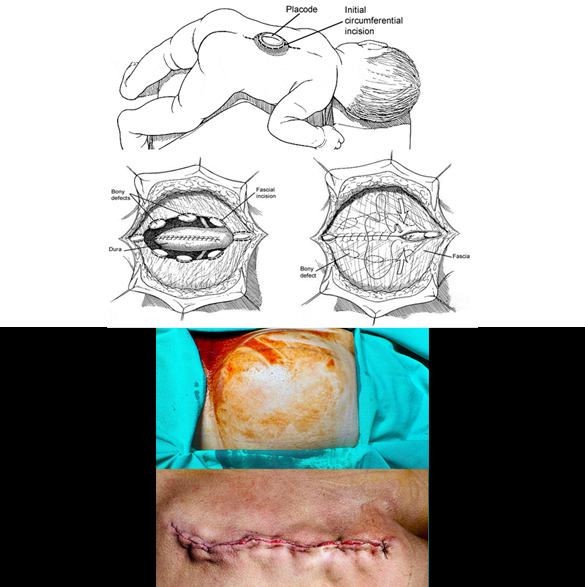

Spina Bifida Surgery

Spina bifida surgery is performed as an open surgical procedure under microscope or surgical loupes. This surgery involves reconstruction of the vertebral column, closing the open congenital defect. The goal of the surgery include prevention of infection, protection of spinal cord and addressing potential complications. Spina bifida surgery should be performed as early as possible after its diagnosis. Early surgery shows better outcome with less complications. While surgery can repair the defect, it cannot reverse nerve damage that has already occurred. Associated problems like hydrocephalus may require detailed investigations prior to surgery. Few complications of the surgery may be wound infection, hydrocephalus, cerebrospinal fluid (CSF) leak, and weakness or paralysis.